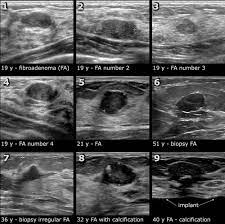

On ultrasound it will be hypoechoic with spiculations radiating away from the nipple. Radiographic features ultrasound malignant characteristics (with positive predictive values) Ultrasound imaging allows better evaluation of the status of the axillary lymph nodes in patients with ibc, an important step in determining extent of disease prior to initiation of chemotherapy. Is the abnormal enlargement of rudimentary male breast tissue. You might get a breast ultrasound: Breast cancer is among the most common causes of cancer deaths today, coming fifth after lung, stomach, liver and colon cancers. Many cancers are not visible on ultrasound. Breast cancer usually makes or presents as a mass or tumor or a lump. This type of cancer also changes the appearance of your breasts. Papillary dcis, a special variant, will show up as matter within the ducts, like a clog within a pipe. It is the most common cause of cancer death in women. in 2005 alone, 519 000 deaths were recorded due to breast cancer. this means that one in every 100 deaths worldwide and almost one in every 15 cancer deaths were due to breast cancer. Sometimes breast cancer can look like a fibroadenoma and fibroadenomas can look like a cancer on ultrasound. Many calcifications seen on mammography cannot be seen on ultrasound.

Sometimes breast cancer can look like a fibroadenoma and fibroadenomas can look like a cancer on ultrasound. Some early breast cancers only show up as calcifications on mammography. Breast cancer usually makes or presents as a mass or tumor or a lump. Rather, the right breast is seen as smaller than the left breast. On ultrasound, a breast cancer tumor is often seen as hypoechoic, has irregular borders, and may appear spiculated.

Why Your Breast Density Matters Cancerconnect from news.cancerconnect.com Sometimes breast cancer can look like a fibroadenoma and fibroadenomas can look like a cancer on ultrasound. You might not need any further tests if everything looks normal. What does a solid mass look like in an ultrasound breast image? The images that a breast ultrasound produces are in black and white. This type of cancer also changes the appearance of your breasts. In the table the differences in ultrasound appearances are listed. Breast cancer is among the most common causes of cancer deaths today, coming fifth after lung, stomach, liver and colon cancers. Many cancers are not visible on ultrasound.

Breast ultrasound is an imaging test that uses sound waves to look at the inside of your breasts. Ultrasounds are usually quick and most don't require special preparation. If your breast tissue is too dense for a mammogram. When is breast ultrasound used? Not all suspicious breast lesions will direct in appearance and ultrasound diagnosis. This high amount of echo results in a bright white spot appearing on the ultrasound image. You can get dressed straight after the ultrasound. Ibc is a rapidly progressive, aggressive form of breast cancer associated with a low overall survival rate. On ultrasound, a breast cancer tumor is often seen as hypoechoic, has irregular borders, and may appear spiculated. In the table the differences in ultrasound appearances are listed. Is the abnormal enlargement of rudimentary male breast tissue. This test is often used when a change has been seen on a mammogram or when a change is felt. Breast cancer usually makes or presents as a mass or tumor or a lump.